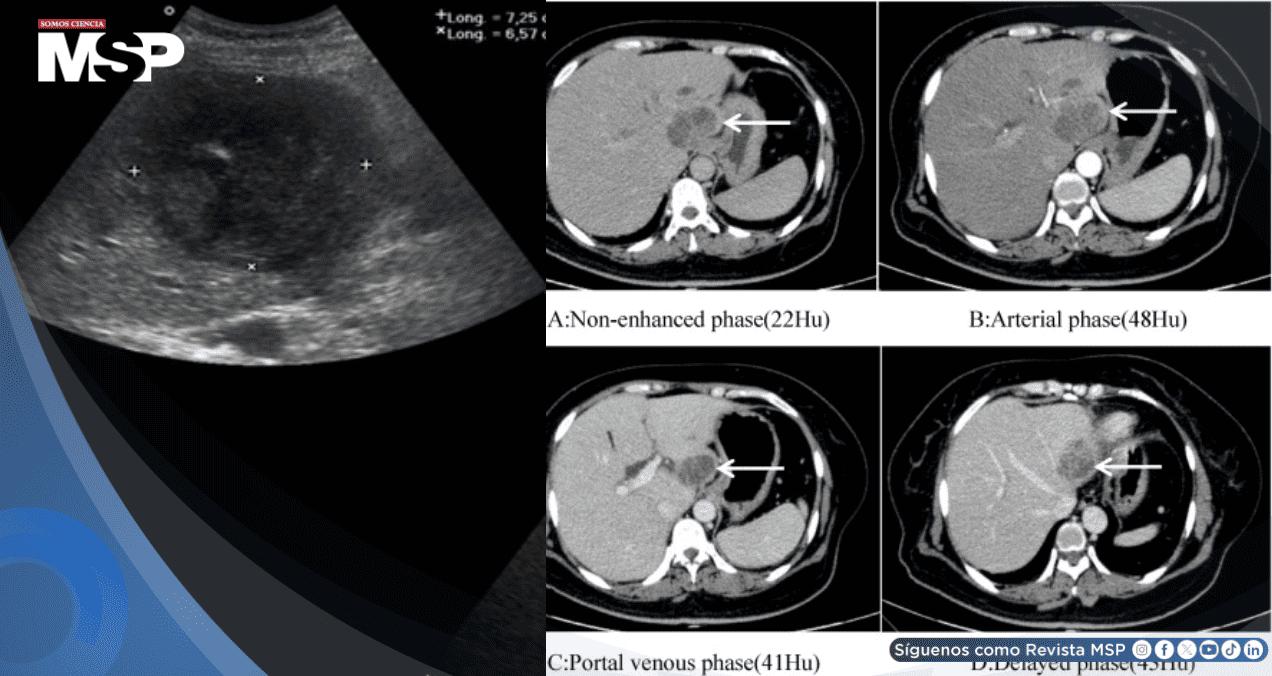

La medición de glucosa en sangre mostró un valor dramáticamente elevado de 25.7 mmol/L, mientras que una tomografía computarizada abdominal completa identificó la verdadera causa del problema: un absceso hepático de tamaño considerable (44 x 42 mm). Estos hallazgos explicaban la falta de respuesta al tratamiento inicial y orientaron el manejo hacia una condición infecciosa grave asociada a diabetes no diagnosticada.

Después de varias semanas de tratamiento antiinfeccioso dirigido, el absceso hepático mostró una reducción notable en su tamaño, disminuyendo hasta 19.15 mm, y la paciente experimentó una recuperación progresiva de todos sus síntomas.